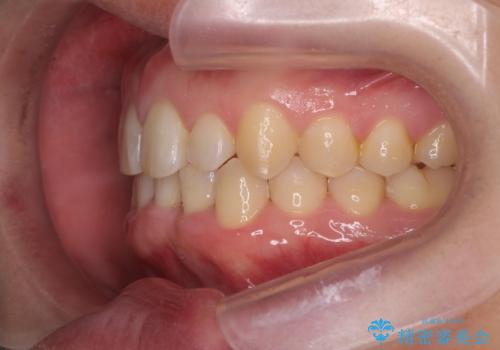

前歯のすき間 歯のがたつき

- 前歯のすき間とがたつきを主訴に来院。

右上の前歯は過去にがたつきがあったとのことで抜いてしまっていました。

歯の数を合わせるために、下の歯を1本抜いて矯正しています。

下の前歯を抜歯したことでブラックトライアングルができましたが、仕上げにIPRを加えることで目立たなくすることができました。